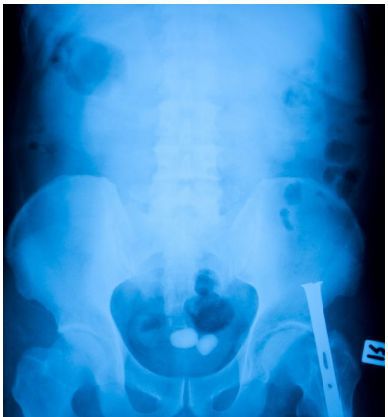

Камни мочевого пузыря могут оставаться в мочевом пузыре в течение некоторого времени и при этом не всегда вызывать симптомы. Их часто обнаруживают «случайно», когда рентген проводится по другой причине.

- Сканирование компьютерной томографией (КТ): КТ-сканирование объединяет несколько рентгеновских изображений для создания подробного изображения внутренних органов;

- Рентген: однако, не все типы камней мочевого пузыря могут отобразиться на рентгеновском снимке;

- Внутривенная пиелограмма: специальная жидкость вводится в вены и проходит через почки и мочевой пузырь. Рентгеновские лучи применяются во время процедуры, чтобы искать признаки камней в почках.